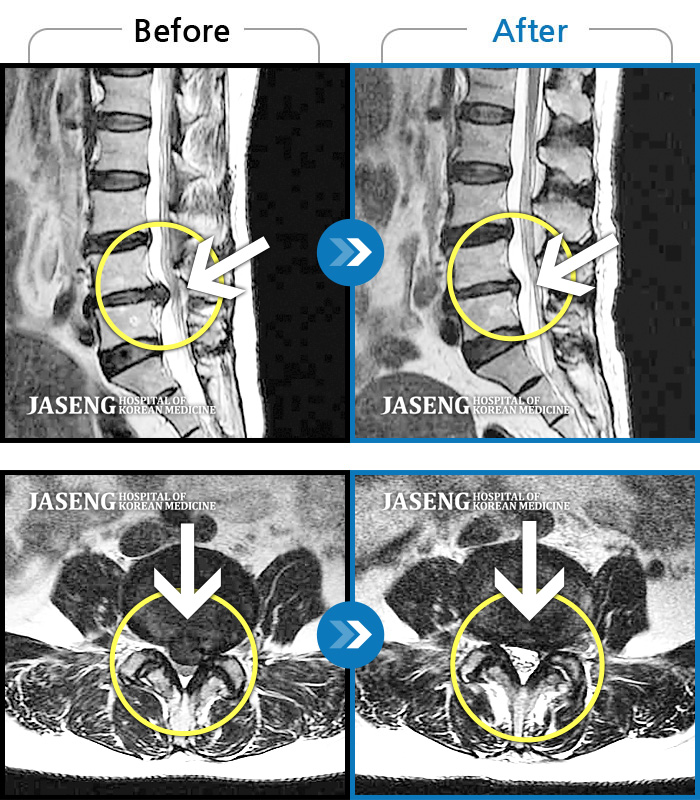

7월 중순경 허리디스크때문에 걷지도 앉지도 못하고 잠도 못 잘만큼 고통 이 심했는데 침과 추나요법 치료를 받고 지금은 통증없이 잘 지내고 있습니다...

친절하게 잘 치료해주신 김 민수 원장님께 감사드립니다~~